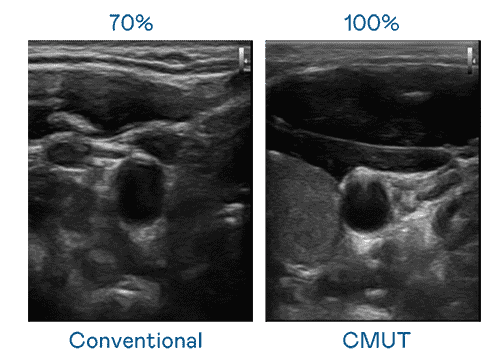

CMUT 技术是一种用电容式微机电元件来产生超音波讯号的技术。。。与传统 PZT 压电式技术相比,,CMUT 频宽增加 30%,,,,更宽频的超音波讯号让影像解析度大幅提升,,是实现高影像品质医疗超音波扫描、、促进精准医疗发展的关键技术。。。。

大频宽带来超清晰影像

超音波影像的解析度高低,,,首先取决于探头能发出的讯号频宽。。。PA直营 CMUT 可提供高清晰的超音波讯号,,提供高频宽、、高灵敏度、、、、影像纹理细节更高的超音波影像,,,协助医护人员缩短影像判读时间及利用精准的医疗影像进行诊断。。。